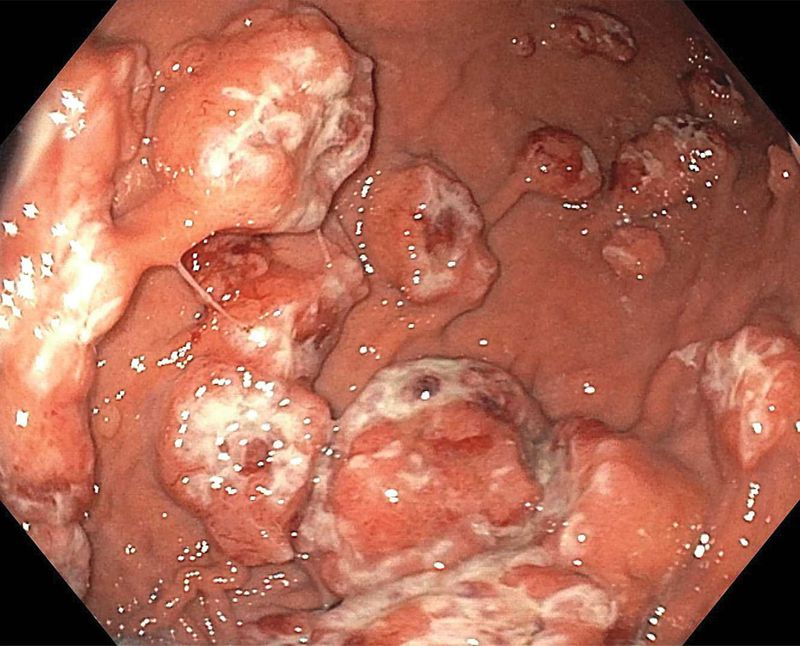

An 85-year-old man presented to the emergency department after losing consciousness and collapsing. He had regained consciousness by the time of presentation and reported a 2-week history of passing dark stools. He had a history of two cancers: breast cancer, for which he was receiving treatment with goserelin and letrozole, and nodular melanoma, for which he had undergone a wide local excision on the right arm and dissection of the axillary lymph nodes 5 months earlier. The heart rate was 110 beats per minute, and the blood pressure was 115/70. He was pale, and there was evidence of ongoing melena with no abdominal tenderness. Laboratory studies showed a hemoglobin level of 7.6 g per deciliter (normal range, 11.5 to 15.5), and he received 1 unit of red cells. Endoscopy revealed multiple polypoid nodules with a central depression and evidence of recent, but not active, bleeding in the stomach. The results of histologic analysis of biopsy samples were consistent with metastatic melanoma. Computed tomography showed thickening of the stomach wall and lining, along with metastases in the brain, lung, and liver. Despite treatment with palliative radiation and pembrolizumab, he presented 3 months later with further episodes of melena as well as multiple other complications. He was transitioned to hospice care and died shortly thereafter.